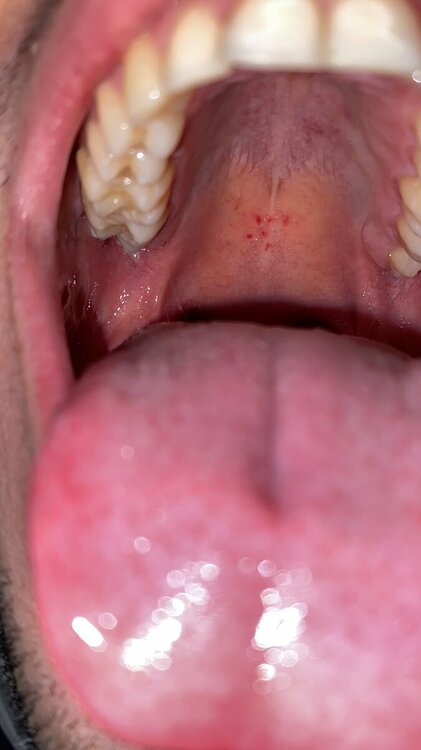

Salve dottore,

stamattina mi sono svegliato con queste macchie nel palato della bocca? Cosa possono essere? C’è da preoccuparsi?

traumatismo al palato

Io stamattina mi sono svegliata così è preoccupante? Vi prego rispondete urgentemente